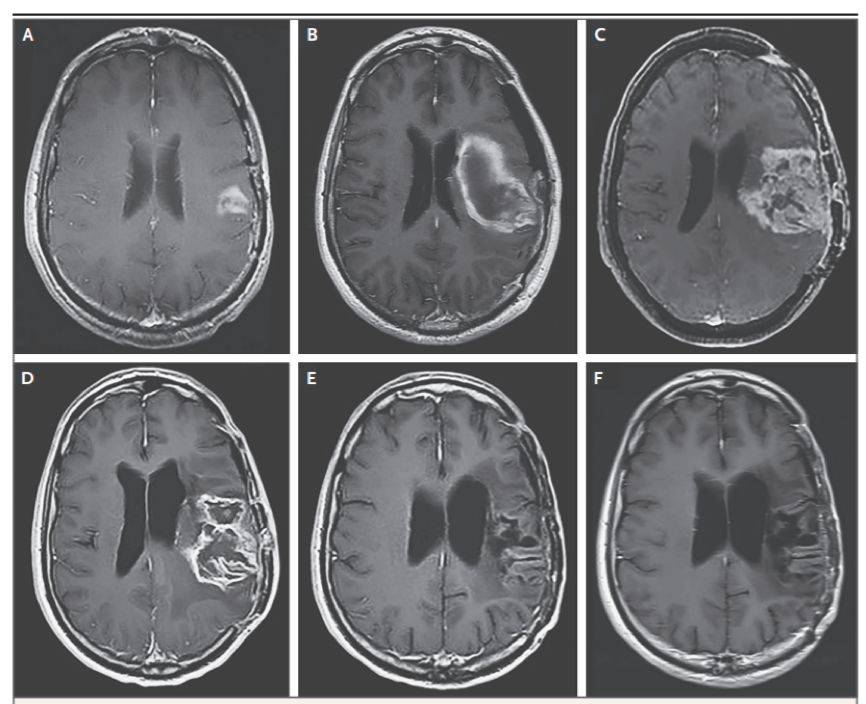

比如下面这位。

图A是治疗前的肿瘤,图C是溶瘤病毒治疗后,肿瘤进展。可以看出,这个时候肿瘤已经又长大了。医生只好换了一种叫洛莫司汀的化疗药物,试验宣告“失败”。

谁也没想到,仅一个疗程,肿瘤就开始出现好转(图D),到一年后,肿瘤已经完全消失了。即使停掉化疗一年后,肿瘤依然没有任何复发迹象(图F)。随访五年时,这个患者还活得好好的!